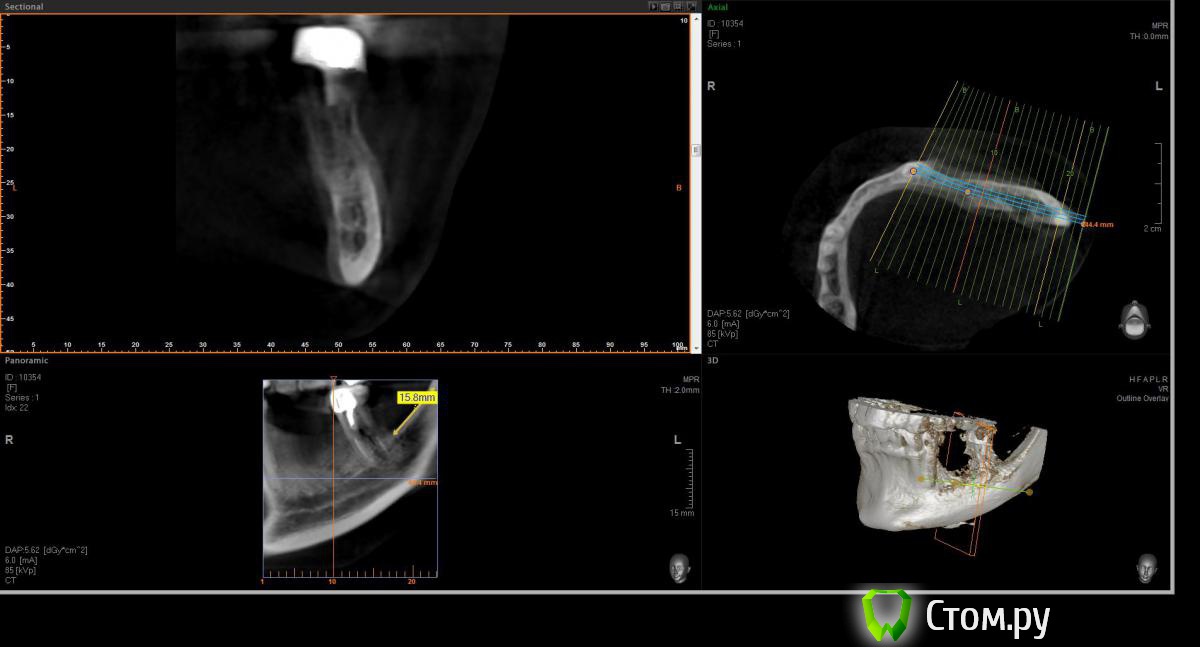

Opimar Опубликовано 21 июня, 2014 Поделиться Опубликовано 21 июня, 2014 Здравствуйте коллеги. Прошу вашей помощи и совета с пациенктой. В анамнезе травматичное удаление около 2-3 лет назад 35-36. Со слов пацинтки удалялось долотом и в 2 приема, вообщем по прошествию времени результат плачевный К мостовидному протезу пациентка не готова, очень хочет лечение с имплантантами и готова к костной пластике. Восстановить такой дефект ,если я правильно понимаю, более-менее прогнозируемо можно только с трансплантацией аутокостных блоков. Как раз по типу того как выкладывал Mane http://forum.stom.ru/topic/25799-kk-monokortikalnye-bloki/ либо по Кюри. Сам склоняюсь к забору блока с наружной косой линии или с подбородка. С блоками работать буду первый раз. Прослушал курсы Томаса Хансера. Прошу высазать идеи и предложения,возможны ли альтернативные методы? Кт прилагаю. Спасибо Ссылка на комментарий

Opimar Опубликовано 21 июня, 2014 Автор Поделиться Опубликовано 21 июня, 2014 Выкладываю еще. Пошагово от 34-37 Ссылка на комментарий

Bier Опубликовано 21 июня, 2014 Поделиться Опубликовано 21 июня, 2014 Выкладываю еще. Пошагово от 34-37темная точка достаточно высоко, это по моему не нерв, нерв ниже, я правильно понимаю? Ссылка на комментарий

Opimar Опубликовано 21 июня, 2014 Автор Поделиться Опубликовано 21 июня, 2014 темная точка достаточно высоко, это по моему не нерв, нерв ниже, я правильно понимаю?Да он ниже и язычнее. Провел от менталиса там еще запас есть. Ссылка на комментарий